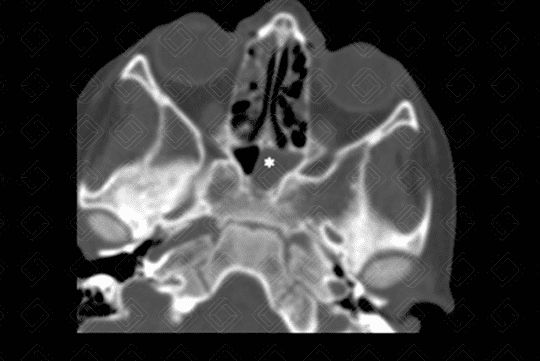

Texto alternativo para a imagem Figura 1. Créditos: Dra Elazir Mota - Rio de Janeiro/RJ

Descrição da lesão: Tomografia computadorizada de seios da face com cortes axiais, seguida de reconstruções coronais. Preenchimento completo do seio maxilar direito (seta branca na figura 1) e parcial das células etmoidais bilateralmente (setas vermelhas na figura 2), associado à obliteração do infundíbulo deste lado. Observa-se, ainda, espessamento mucoso concêntrico do seio esfenoidal esquerdo (asterisco na figura 3).